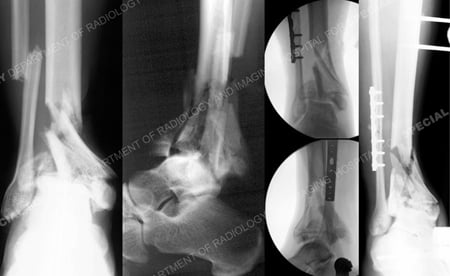

Anteroposterior and lateral radiographs illustrating a right-sided displaced distal tibial pilon fracture with extensive articular comminution and associated displaced fibula fracture and (right images) fluoroscopic and anteroposterior x-ray following placement of external fixation and ORIF of the fibula fracture.